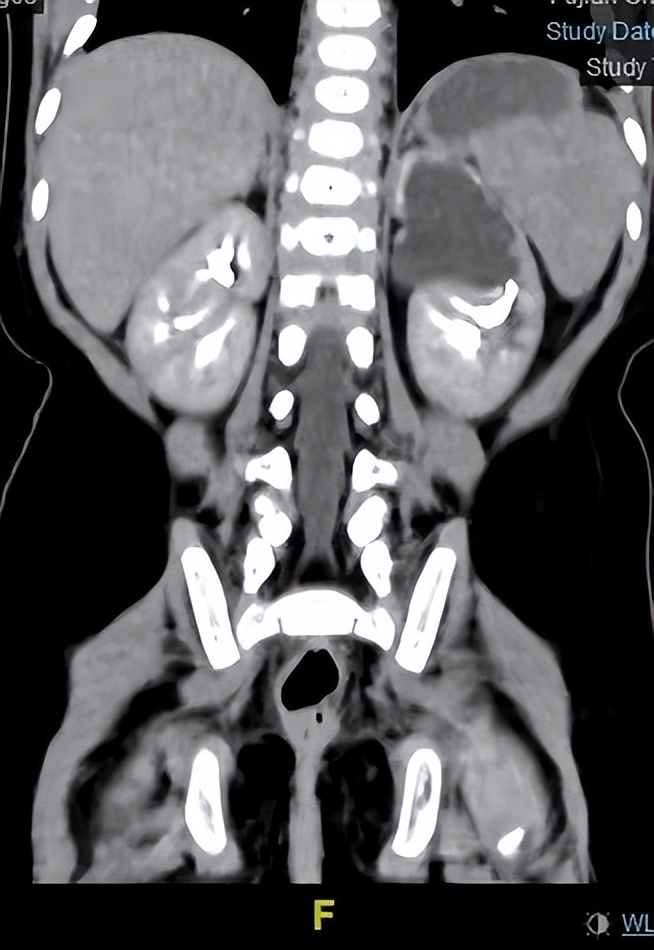

通俗地说,就是一个肾有两套的肾结构,是两套相互独立的肾盂肾盏系统,一个肾重复畸形具有上肾和下肾两个单位,可分别由两根输尿管引流各自集合系统的尿液,称为重复输尿管( 引流上肾或者下肾的输尿管分别被称为“上肾输尿管”和“下肾输尿管”)。在临床上,重复肾还是比较常见的。有研究发现,每1500个小孩中就有1个重复肾小孩。重复肾可以是单侧的,也可以是双侧的,单侧更多见。

根据两根输尿管是否汇在一起,可分为完全性和不完全性( Y 形)两种。不完全性重复尿管可以汇合于输尿管的任何部位,较为常见的是肾盂输尿管连接部相连,或输尿管连接于远端接近膀胱水平。

4、彩超联合CTU检查,可明确绝大部分重复肾和重复输尿管。

6、静脉尿路造影,如重复肾有功能,造影时可显示两个肾盂肾盏;如无功能,则仅显示一低位肾。逆行尿路造影时如插管成功,显影较清晰,更有助于诊断。